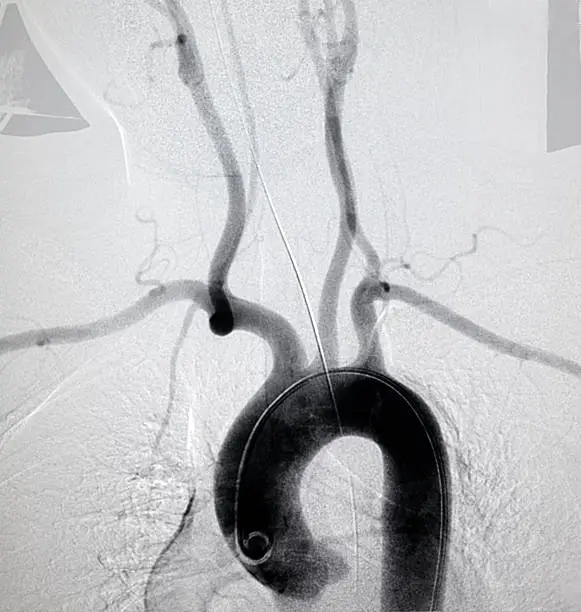

내부 장기에 발생한 해면상 혈관종의 경우에는 수술이 필요할 수 있습니다. 수술은 종양을 완전히 제거하거나, 크기를 줄여 주변 조직에 대한 압박을 완화시키는 데 중점을 둡니다. 그러나 수술은 신경이나 중요한 장기에 가까운 경우 위험할 수 있으므로 신중한 계획이 필요합니다. 이 외에도 스테로이드나 베타 차단제와 같은 약물 치료가 해면상 혈관종의 크기를 줄이는 데 효과적일 수 있습니다.

해면상 혈관종의 진단은 주로 임상적인 관찰을 통해 이루어집니다. 의사는 환자의 병력을 조사하고 종양의 모양과 크기, 촉감을 확인하여 해면상 혈관종인지 여부를 판단합니다. 필요에 따라 초음파나 MRI와 같은 영상 검사를 통해 혈관종의 정확한 위치와 크기, 주변 조직과의 관계를 확인할 수 있습니다. 특히, 내부 장기에 발생한 혈관종은 이러한 영상 검사를 통해 더욱 정확하게 평가됩니다.